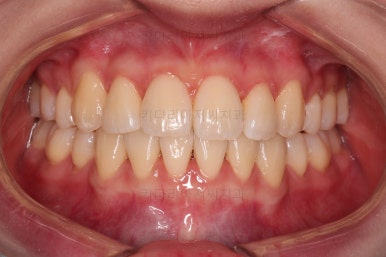

마찬가지로 초진 시 입안의 모습인데요.

전반적으로 약간 삐뚤지만 특히 윗니 앞니가 삐뚤고요.

송곳니는 덧니처럼 튀어나와 보이네요.

그리고 전반적으로 치아가 앞쪽으로 경사되어 있어서 앞니는 뻗친 느낌이 있네요.